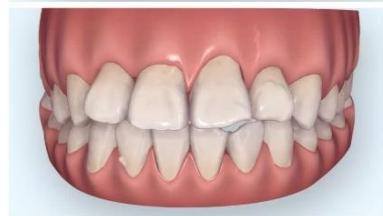

Intraoral examination revealed severe proclination and protrusion of both the maxillary and mandibular incisors [6]. The occlusal relationship was Class I at the canine (tooth 3) and first molar (tooth 6) levels bilaterally. A critical unfavorable biological factor was the proximity of the mandibular incisor roots to the labial cortical plate, representing a high-risk condition when planning extraction-based anterior retraction mechanics [10-12]. All four third molars were present.

Figure 2: Pre-Treatment Intraoral Photographs

Figure 3: Pre-Treatment Intraoral 3D Digital Models